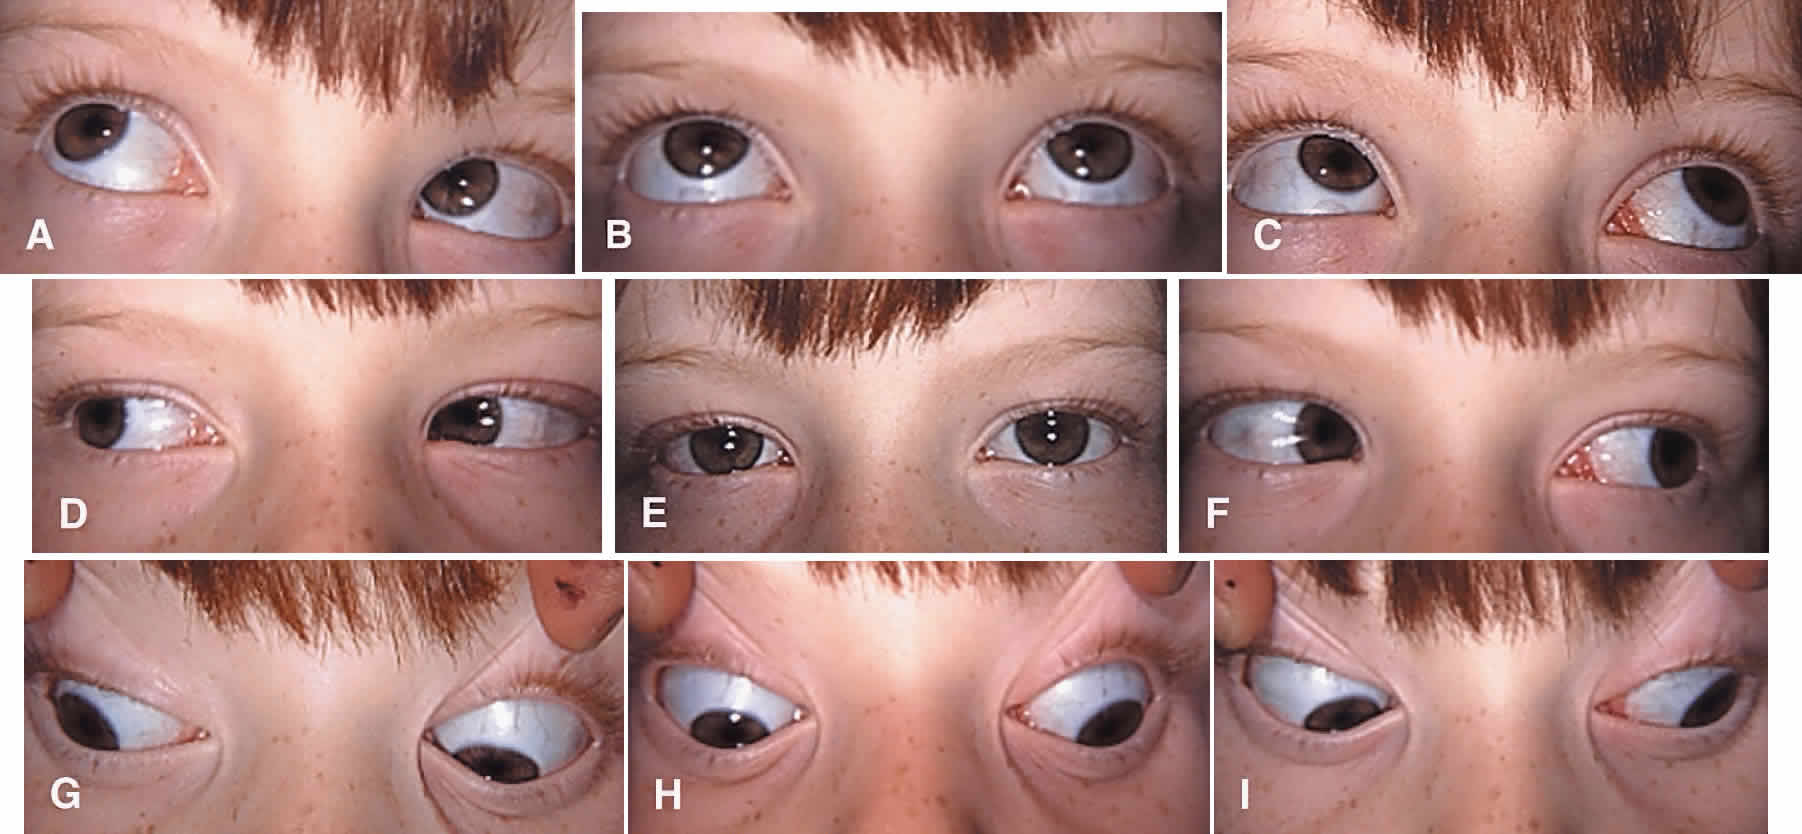

Successful results can be achieved with various surgical approaches (Fig. 2).29–36 Superior oblique muscle strengthening operations are usually performed in conjunction with surgery on other cyclovertical muscles. Their most common uses are (1) to augment ipsilateral inferior oblique muscle weakening in patients with at least 30 diopters (D) of hypertropia in lateral gaze or 20 D of hypertropia in primary gaze; (2) to augment ipsilateral superior rectus or contralateral inferior rectus muscle recession or posterior fixation in patients with increased hypertropia in down gaze; (3) to correct excyclotropia in the presence of a small hypertropia in primary gaze position; and (4) to improve the function of a congenitally lax or redundant tendon.37 In fact, torticollis may be difficult or impossible to eliminate in some children without a superior oblique tendon tuck or similar strengthening procedure.38 The Harada-Ito procedure and its modifications enhance intorsion and are used to correct excyclotropia when little or no vertical misalignment in primary gaze position exists.39–41 Its use, therefore, is limited primarily to correcting torsional diplopia in patients with bilateral superior oblique muscle palsy. Small horizontal deviations associated with superior oblique muscle palsy tend to resolve spontaneously after vertical realignment of the eyes. In our experience, concurrent horizontal rectus muscle surgery often (and for unknown reasons) leads to overcorrection and is usually unnecessary.

The superior oblique tendon can be resected or advanced in a manner similar to that used for rectus muscles (see Fig. 2C). However, the long and fanlike tendinous insertion makes this technique more challenging, even with optimal exposure, and typically results in narrowing and some anterior transposition of the scleral insertion. Furthermore, this procedure is less easily reversible than superior oblique tendon tuck and other nondisinsertion procedures. Therefore, superior oblique tendon resection is rarely, if ever, selected by most surgeons.

The Harada-Ito procedure is usually indicated in patients whose primary complaint is torsional diplopia (Fig. 2E, F and Fig. 8). This is encountered most often in adult patients with bilateral, posttraumatic superior oblique muscle palsy. Patients with congenital superior oblique palsy often have sensory adaptations that partially or completely compensate for years of excyclotropia. Although used primarily to correct symptomatic excyclotropia in patients with little or no vertical deviation in primary gaze position, it may also be effective in the treatment ocular torticollis with tilt-dependent nystagmus.52,53 The Harada-Ito procedure involves selective strengthening of the anterior fibers of the superior oblique tendon that are primarily responsible for incyclotorsion. It can be performed either by disinserting, advancing and anteriorly transposing the anterior tendon fibers (disinsertion technique) as described by Fells54 or by the classic Harada-Ito method, which redirects the anterior fibers as a “dog leg” without scleral disinsertion (Fig. 8).40 We prefer the classic method because it is more easily reversible. However, the disinsertion technique has the advantage of being readily modified for use with adjustable sutures.41,55 Superior oblique tendon tuck limited to the anterior fibers is an occasionally useful alternative when an intermediate amount of incycloduction is desired with some vertical correction.